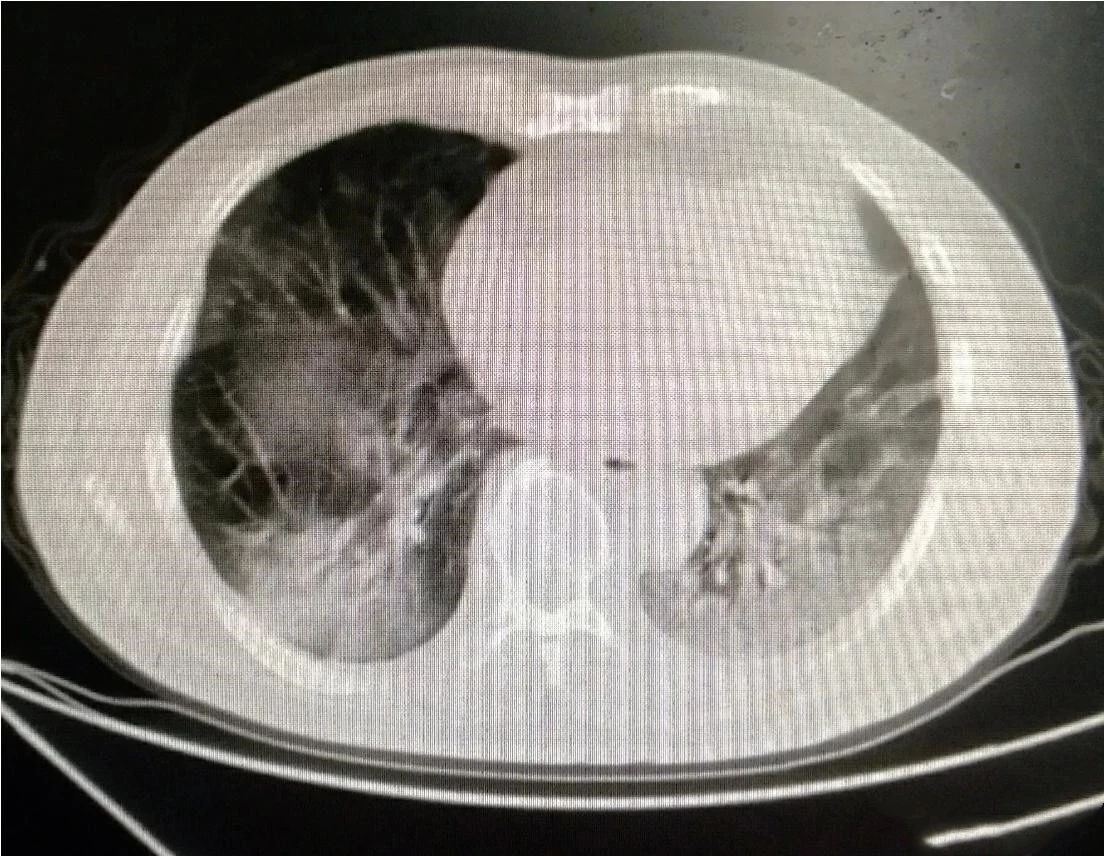

下图是同一位患者三次CT检查的图像,每次检查相隔2天,我们来看看肺部的变化。

大家可以很清楚地看到,右侧(患者的左胸)肺部全变白了,左侧(患者右胸)变白的面积也是非常大。

正常的肺组织里含有大量的空气,对X线的阻挡能力很弱,所以在X线下呈现黑色。当肺部出现炎症反应,大量蛋白、组织液、白细胞等渗出,肺间质充血、水肿等,这时的肺组织对X线的吸收能力就明显增强了,有点像实质器官的表现,所以呈现出白色。

变成白色的肺组织,基本上失去了气体交换的能力,患者会感到明显的缺氧,呼吸困难。我们需要给患者吸氧,重症者上呼吸机,甚至动用ECMO进行治疗。上面我举例的这位患者,就是一位新型冠状病毒感染的患者,最终由于病情发展太快,而不幸死亡。